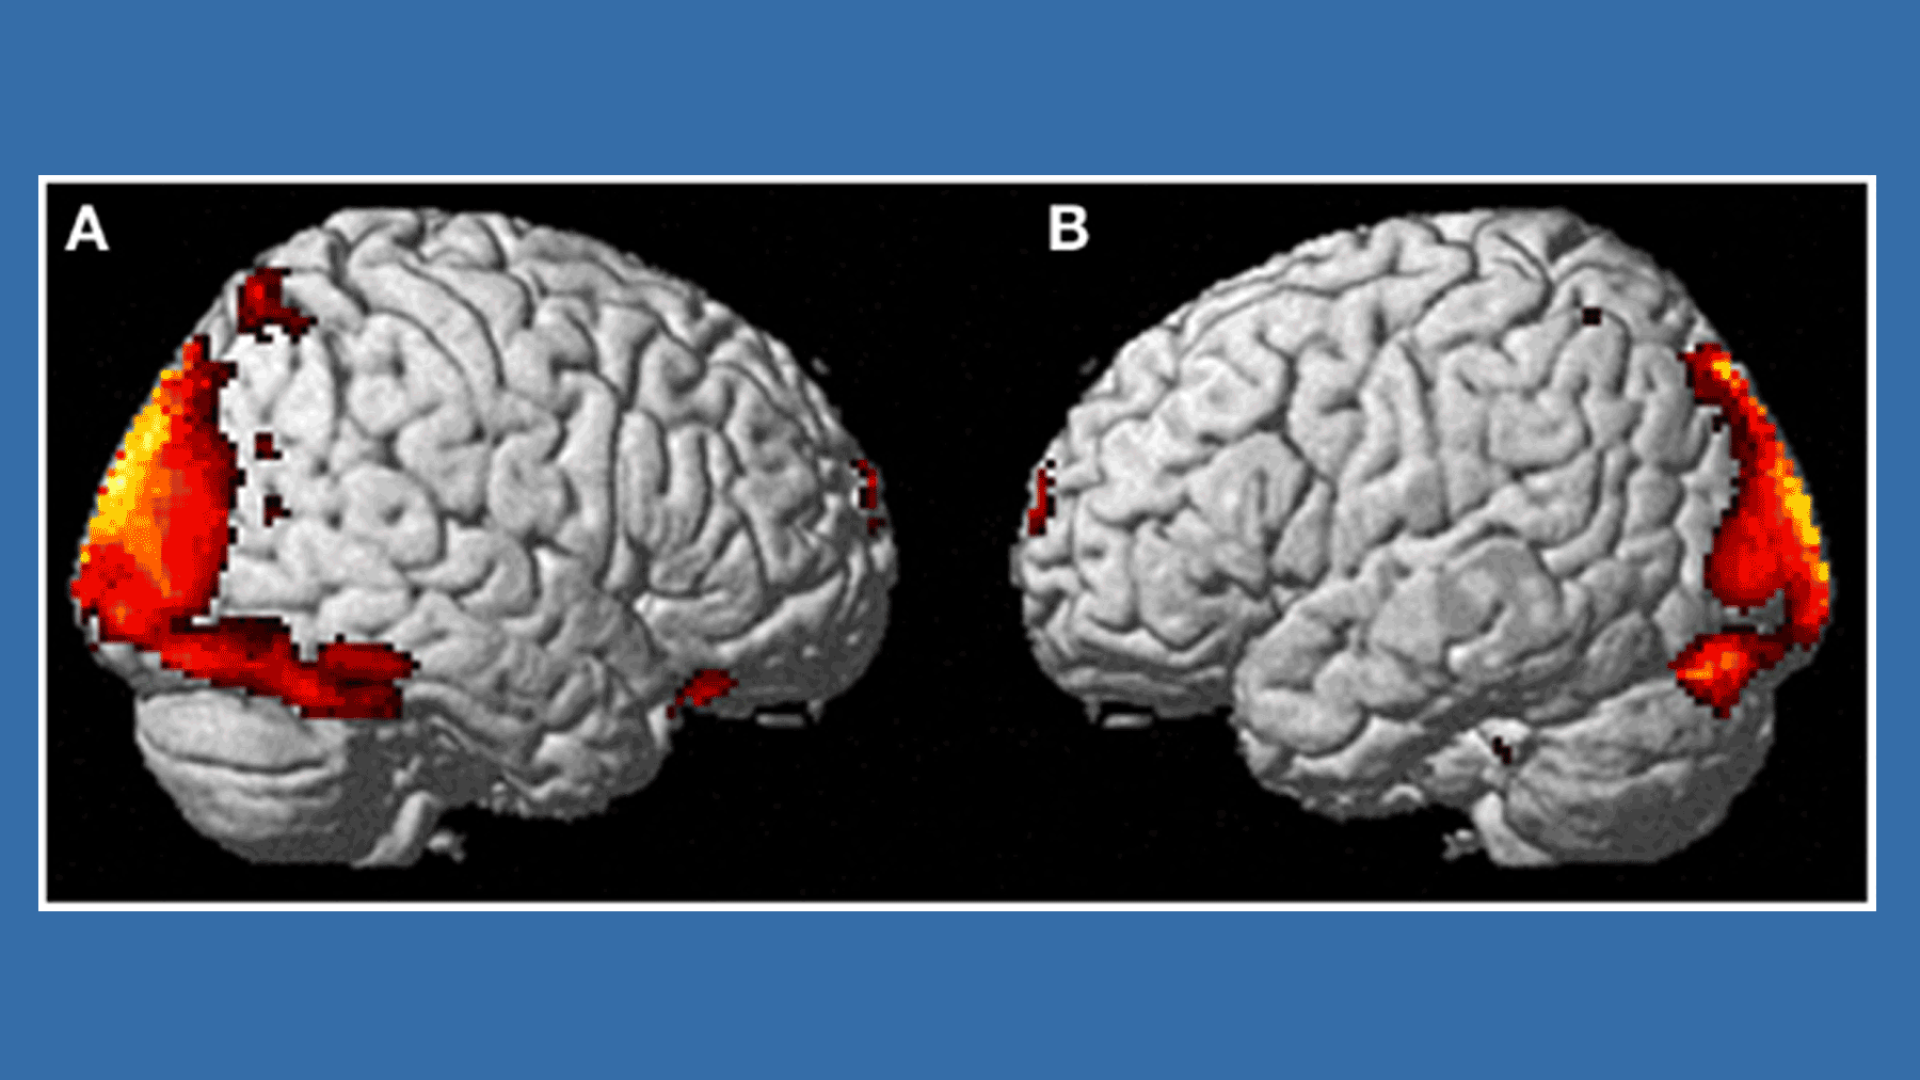

Kokeen aikana nainen oli magneettikuvauslaitteessa, joka seurasi koko ajan hänen aivojensa toimintaa. Aivojen näköaivokuori aktivoitui voimakkaasti kokemuksessa ja samalla aivojen vasemman puolen liikeaivokuoren alueet, joiden tiedetään olevan yhteydessä mielikuviin sekä raajojen sekä koko kehon liikkeisiin muuttuivat selvästi aktiivisemiksi. Tämän aivojen alueen avulla tiedostamme missä olemme ympäristössämme ja kuinka liikumme siinä.

Nähtävästi siis koehenkilö simuloi tapahtumaa koko ajan aivoissaan, sillä samaan aikaan hänen oma kehonsa oli tukevasti paikallaan, eikä huoneessa tapahtunut mitään epätavallista. Vaikka naisen kannalta tapaus oli hyvin todellinen, oli se tapahtunut vain hänen omissa aivoissaan.